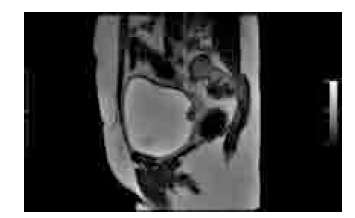

Considerando os achados de imagem representados na figura acima, julgue os itens seguintes.

Os sítios mais comuns de metástases a distância incluem linfonodos, ossos e fígado, e entre os mais raros, destacam-se pulmões e cérebro.